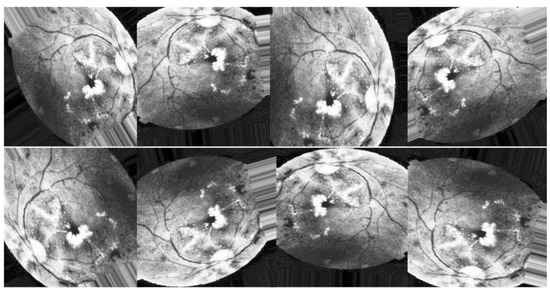

All previous edits to images in the training set are applied to generate new samples for the network. While the total number of images is the same in all scenarios, Figure 8, Figure 9 and Figure 10 illustrate the purpose of data augmentation, which is to increase the quantity of data by providing slightly altered copies of the existing data or newly synthesized data derived from the existing data using the same parameters in all three scenarios. Here are the three scenarios that were used to train DenseNet-121:

Scenario I

In the first scenario, shown in Figure 8, researchers augment the improved images using CLAHE and ESRGAN.

Figure 8. Examples of augmenting the same image with different methods (CLAHE + ESRGAN).